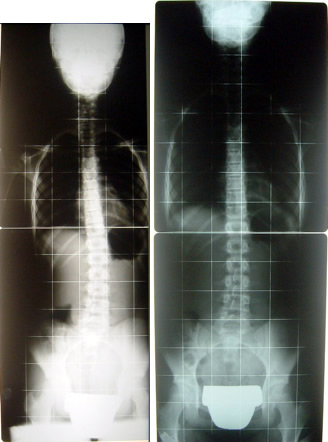

Mädchen, 11 Jahre alt, Skoliose

rechts: nach 12 Monaten